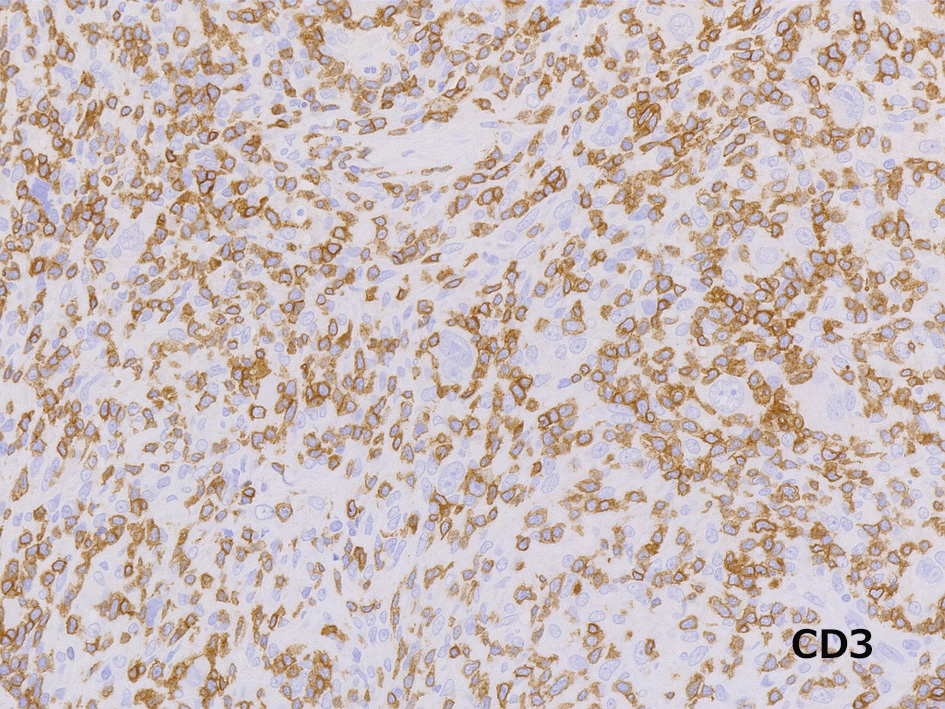

HRS細胞はCD30+,CD15+. CD3+Tリンパ球に取り囲まれている. 結節を形成する小リンパ球はCD20+, IgM+, IgD+のmantle zone cellで, 偏在する胚中心はCD21+のmeshworkで認識される。EBVの陽性率はNSよりは高くMCよりは低い。中程度。

免疫染色

RS細胞は転写因子のBob1, OCT2陰性. PAX5はRS細胞の核に,ごくごく弱い陽性を示している。EBER-ISHは陰性であった。

CD30, CD15は陽性, 転写因子のBob.1, OCT2は腫瘍細胞は陰性となる.